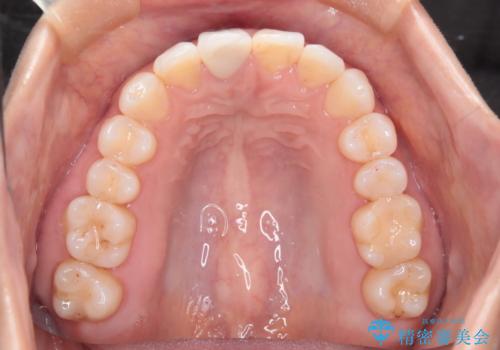

- 前歯のガタつき、変色を主訴に来院された患者様です。術前診査のCT撮影にて、変色した前歯の根の先に病巣があることが判明しました。そこで、マウスピースによる矯正治療と、前歯の根管治療、かぶせ物のやり直し治療を並行して行いました。